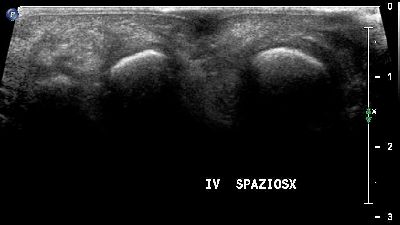

Flogosi plantare (img. 01) flogosi plantare 01